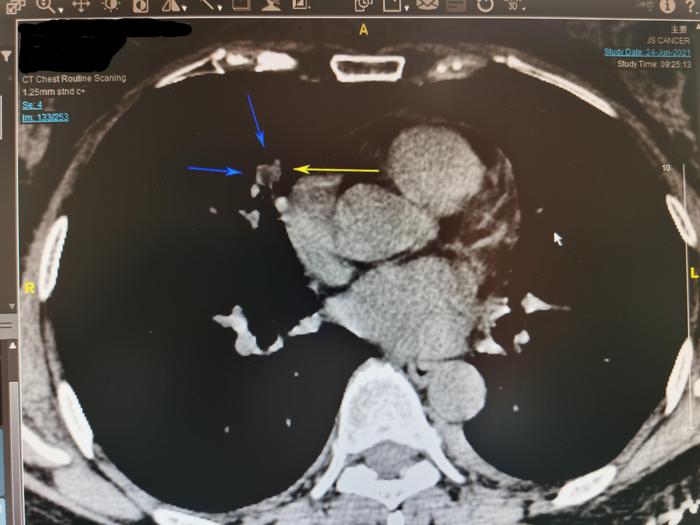

我用三个箭头指示这个右中肺实性结节,在薄层CT133层面,此结节的三条边都比较直。边缘笔直是良性结节的特点。

上图是我把这个结节由肺窗转变为纵隔窗。可见此结节内部局部看起来发暗。

我仔细测量其中一小块发暗的区域,CT值为-62,说明局部有脂肪密度,此实性结节内部有脂肪成分。有脂肪成分的实性肺结节一般是良性肺结节。